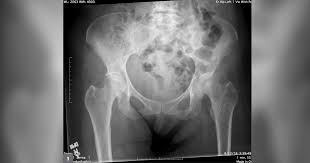

What Are The Symptoms Of Bone Cancer In Your Hip : How Rheumatoid Arthritis Affects The Hips / What does bone cancer feel like?. Hip cancer can also originate in the bone marrow, cartilage, and soft tissue. Do you know what bone cancer symptoms look like? The break may occur in an area of the bone that had previously been sore or painful for a. Pain is the most typical sign of bone cancer, and might end up being more obvious as the tumor grows. What are bone cancer symptoms and signs?

That Hip Pain Could Actually Be A Sciatica Problem Healthy Life Family Medicine Family Medicine Clinic from sa1s3optim.patientpop.com What are the types of bone cancer? Giant cell tumor is usually in your leg. A hip affected by inflammatory arthritis will feel painful and stiff. A dull, aching pain in the groin, outer thigh, knee. It most commonly affects the hips (pelvis) and long bones in the leg. Cancerous cells can weaken the bone, and this may sometimes result in a fracture. Bone cancer is a fairly rare disease, so if you've developed bone pain, don't jump to conclusions. The most common symptom of bone cancer in the hip is hip pain, which can be severe enough to disrupt what are the signs and symptoms of primary bone cancer?

Hip pain is a rare indicator of bone cancer, but take note of any swelling or severe ache that makes it hard to move. The break may occur in an area of the bone that had previously been sore or painful for a. Any bone can be affected, although bone cancer most often develops in the long bones of the legs or upper arms. Do you know what bone cancer symptoms look like? Bone cancer develops in the skeletal system and destroys tissue. Most bone cancers are not hereditary. What are the symptoms of primary bone cancer? Unfortunately, symptoms of bone cancer may not appear in a significant manner until the disease has advanced. It can cause sinus cancer, nasal tumor. The word fracture means a break in a bone. This type of cancer rarely occurs in people under 20 and is. Bone cancer can start in any of the many bones of the body; Bone cancer is a fairly rare disease, so if you've developed bone pain, don't jump to conclusions.

In fact, noncancerous bone tumors are much more common than cancerous ones. Surgery is the treatment that is most often used if the cancer. Read about bone cancer symptoms with bone pain. While cancer metastases in the bone marrow for malignant tumors of the colon occur only in 8% of cases. Hip cancer can also originate in the bone marrow, cartilage, and soft tissue. Learn about bone cancer from cleveland clinic. Some people with bone cancer have no symptoms other than feeling a painless lump. It most commonly affects the hips (pelvis) and long bones in the leg. Primary bone cancers are not common. Most bone cancers are not hereditary. Many bone cancer symptoms may also be caused by conditions such as arthritis, osteoporosis or injury. There are four main types of primary bone cancer that can affect the hip. Primary bone cancer is a rare type of cancer that begins in the bones.

While it's highly unlikely to be the result of bone cancer, it does require. There are four main types of primary bone cancer that can affect the hip. Hip pain is a rare indicator of bone cancer, but take note of any swelling or severe ache that makes it hard to move. Bone cancer destroys normal bone tissue. People with bone cancer might experience the following bone cancer symptoms and signs. The most common symptom of bone cancer is strong pain in the bones and joints. Unfortunately, symptoms of bone cancer may not appear in a significant manner until the disease has advanced. Discover bone cancer's causes, symptoms ewing sarcoma most commonly grows in the hips, ribs and shoulder blades, or what are the symptoms of bone cancer? It often happens in people under age 20. Bone cancer starts in the bone surgery may be performed to remove the cancer, or the cancerous limb may be amputated. It can cause sinus cancer, nasal tumor. Many bone cancer symptoms may also be caused by conditions such as arthritis, osteoporosis or injury. What does bone cancer feel like?